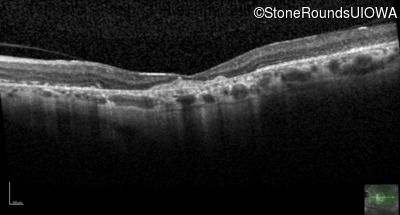

Optical Coherence Tomography - Right - 20/80

Exemplar / OCT Stack

OCT Stack

Optical Coherence Tomography - Left - 20/125